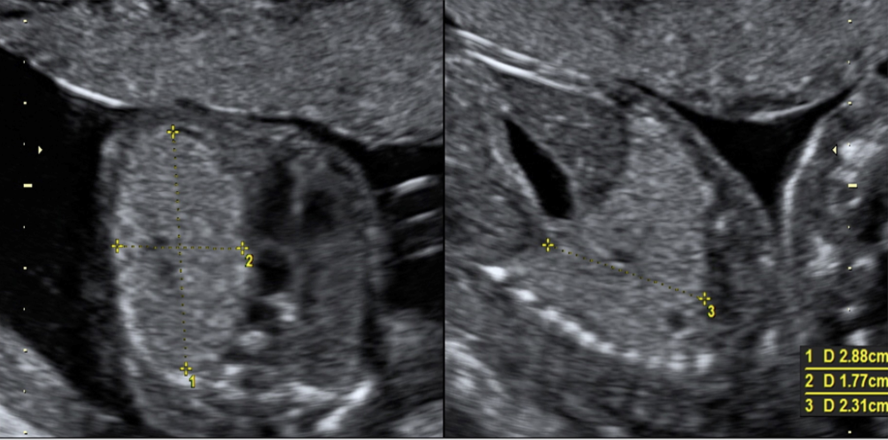

what congenital anomaly is shown

d) posterior urethral valves